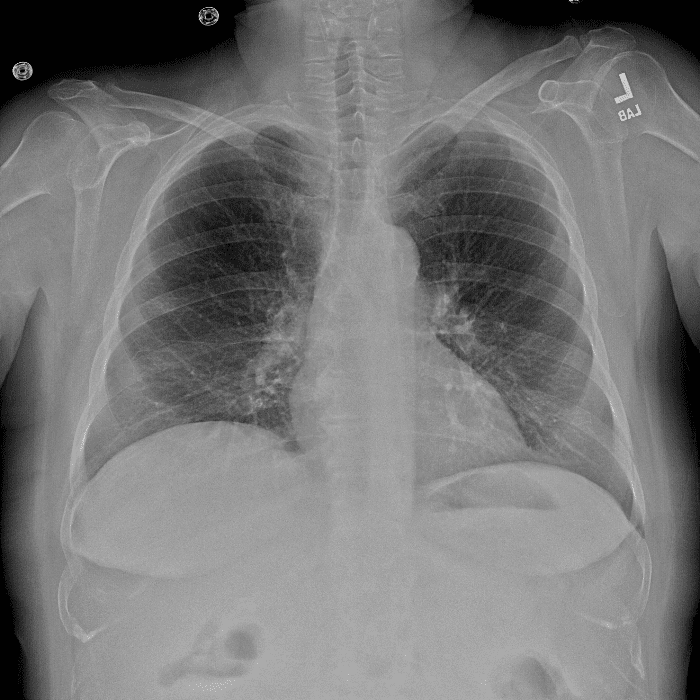

Practice Cases